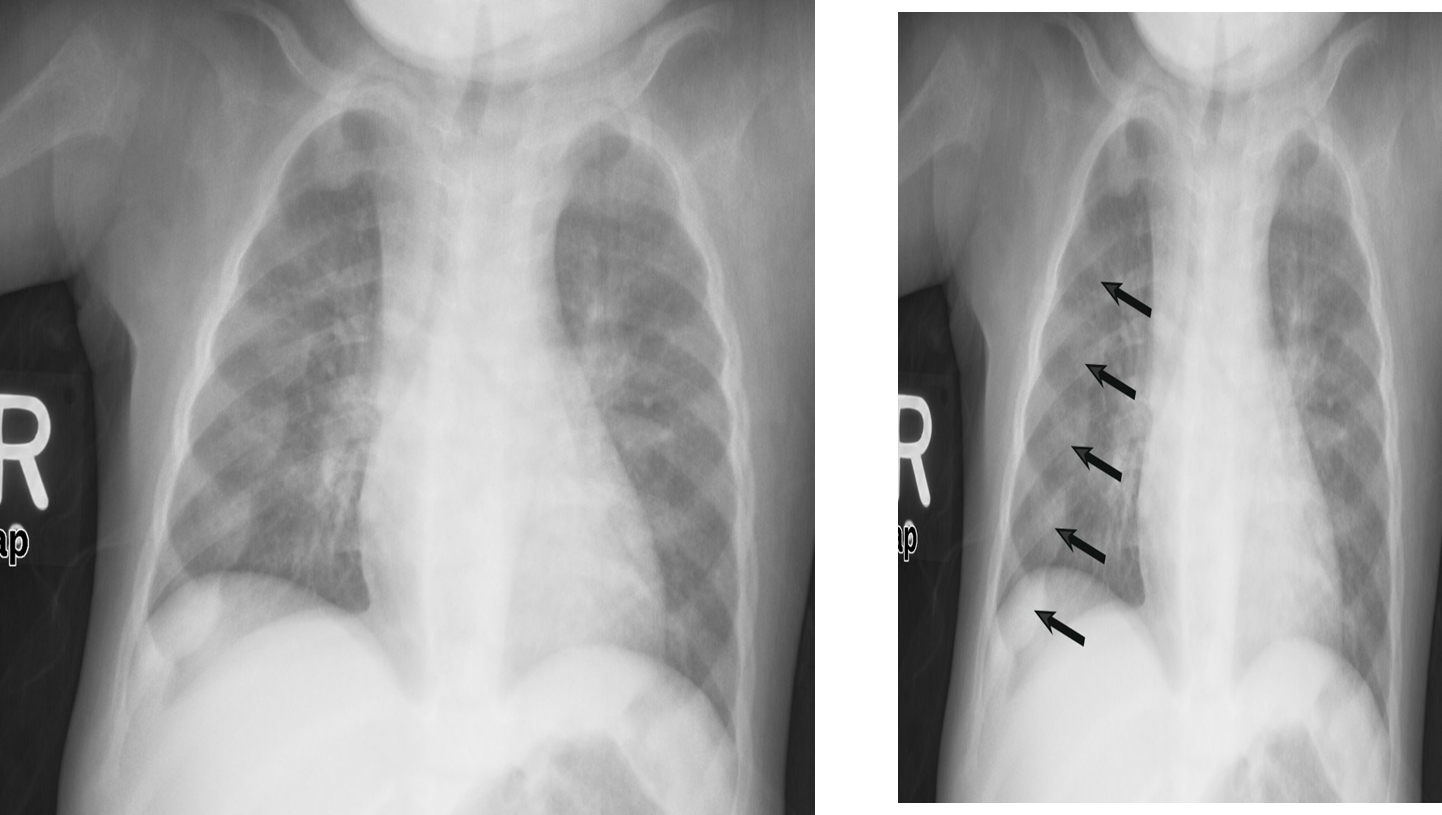

X-ray chest (AP view) of a child.

There are prominent nodular costochondral junctions z (black arrows) on the right side of the chest due to the expansion of the anterior ribs.

These findings are referred to as rachitic rosary because of their resemblance to beads on a rosary.